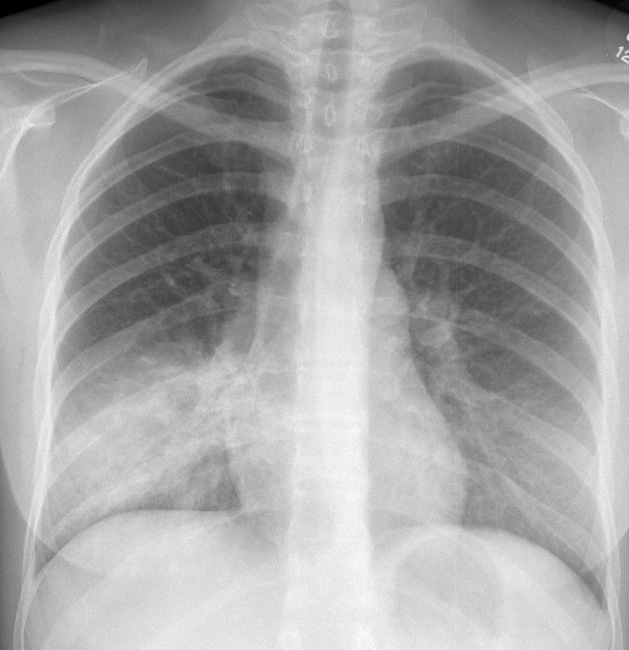

Gallery Pneumonia Case 6 RLL pneum PA

Case 6 RLL pneum PA